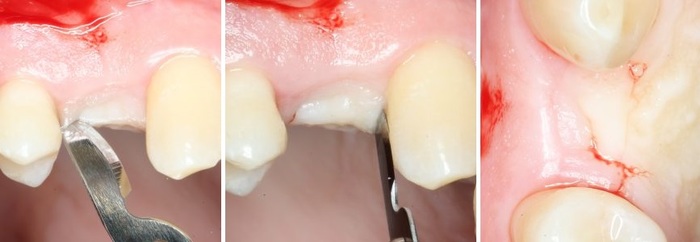

После проведенной анестезии, при помощи скальпеля производится - разрез, а так называемого распатора - скелетирование кости. (отделение надкостницы от компактного вещества кости).

Разрез:

Скелетирование кости: